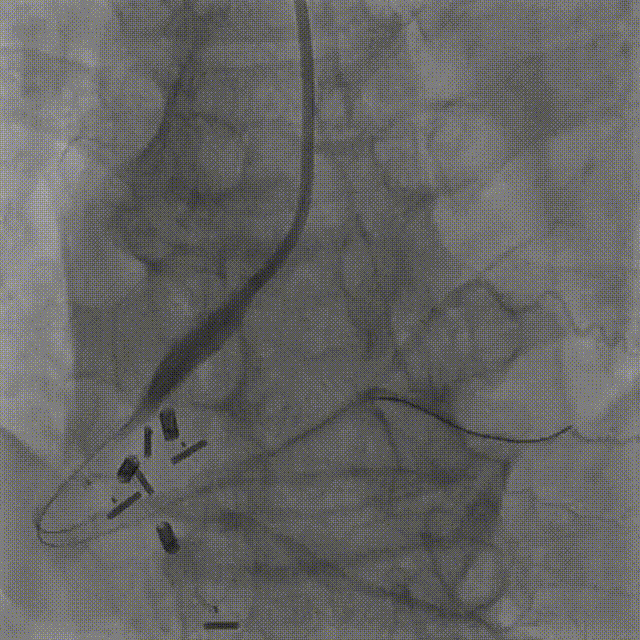

图2 术前三尖瓣环及冠脉CT影像

术前CT评估:患者三尖瓣环面积20.2cm²,瓣环面积巨大。三尖瓣环根部距离右冠状动脉距离风险较高,最近处约6mm左右。